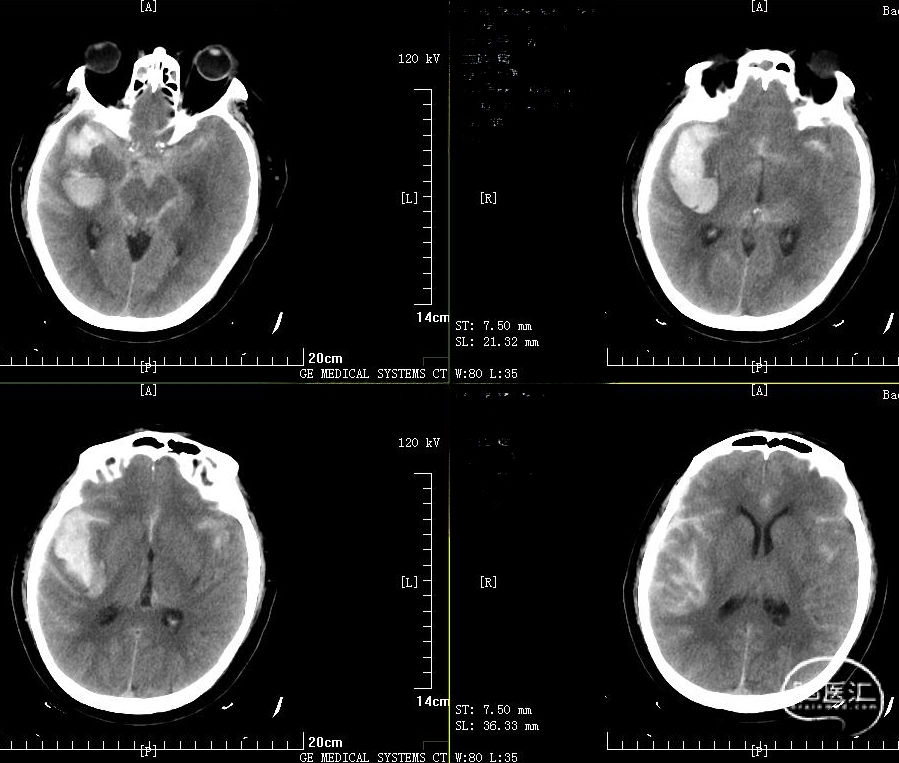

入科后患者意识呈嗜睡状,格拉斯哥评分11分;急诊行脑血管造影提示:右侧大脑中动脉动脉瘤。

2024-05/11急诊造影见右侧大脑中动脉分叉处有一约你10mm*12mm囊状动脉瘤,表面凹凸不平,基地宽,累计中动脉上下干起始部。

1、动脉瘤特点:位于大脑中动脉,囊性,宽基地,累计中动脉上下干分支起始部;M1远端痉挛/纤细;

2、合并右侧颞叶脑内血肿,量约30ml;

3、患者格拉斯哥评分11分;

4、开颅手术难点,术中塑性困难,清除脑内血肿后,可能导致内囊纤维损伤致对侧肢体偏瘫,甚至需要去除骨板减压术;

5、家属坚决要求行介入手术;